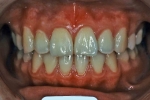

| 初診時